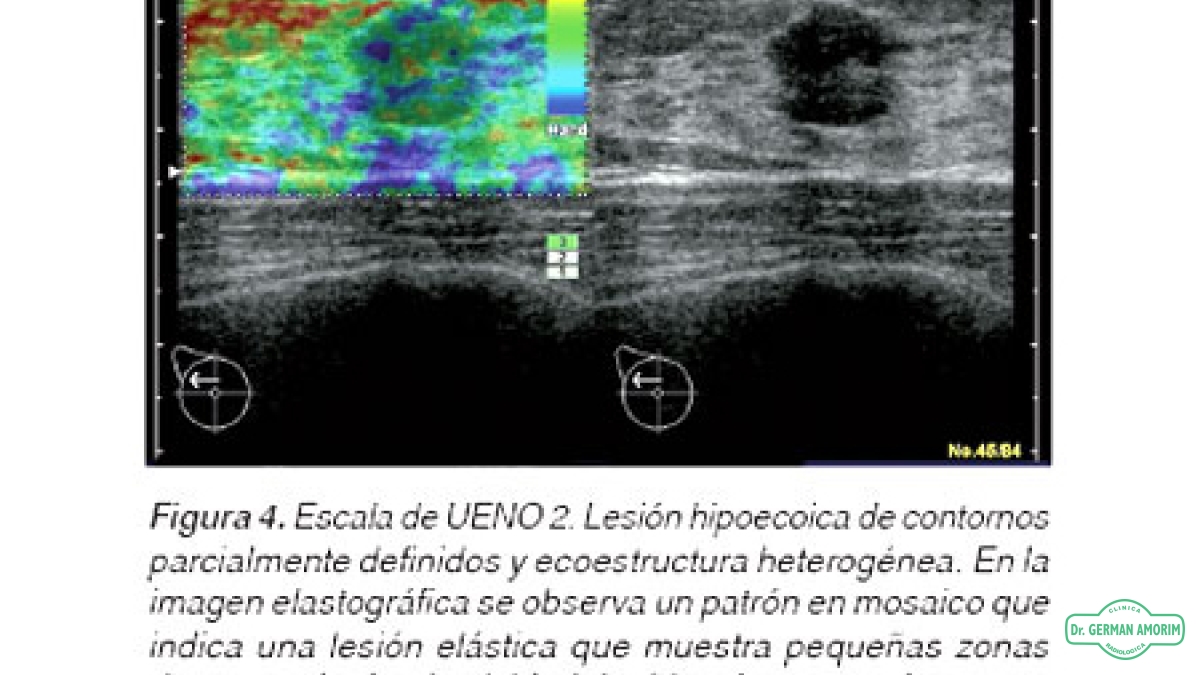

La elastografía es un método de diagnóstico complementario que utiliza los ultrasonidos para valorar la elasticidad o dureza de un segmento de un órgano o de un nódulo en estudio, mediante la tensión y compresibilidad que producen las ondas ultrasónicas en los tejidos del organismo en tiempo real.

Desde su invención, se han descrito múltiples aplicaciones en el estudio de los tejidos de la mama, próstata, tiroides y vasos sanguíneos.